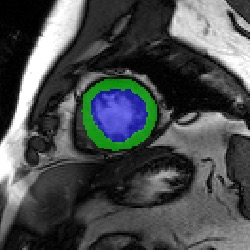

Transformers, the default model of choices in natural language processing, have drawn scant attention from the medical imaging community. Given the ability to exploit long-term dependencies, transformers are promising to help atypical convolutional neural networks (convnets) to overcome its inherent shortcomings of spatial inductive bias. However, most of recently proposed transformer-based segmentation approaches simply treated transformers as assisted modules to help encode global context into convolutional representations without investigating how to optimally combine self-attention (i.e., the core of transformers) with convolution. To address this issue, in this paper, we introduce nnFormer (i.e., Not-aNother transFormer), a powerful segmentation model with an interleaved architecture based on empirical combination of self-attention and convolution. In practice, nnFormer learns volumetric representations from 3D local volumes. Compared to the naive voxel-level self-attention implementation, such volume-based operations help to reduce the computational complexity by approximate 98% and 99.5% on Synapse and ACDC datasets, respectively. In comparison to prior-art network configurations, nnFormer achieves tremendous improvements over previous transformer-based methods on two commonly used datasets Synapse and ACDC. For instance, nnFormer outperforms Swin-UNet by over 7 percents on Synapse. Even when compared to nnUNet, currently the best performing fully-convolutional medical segmentation network, nnFormer still provides slightly better performance on Synapse and ACDC.